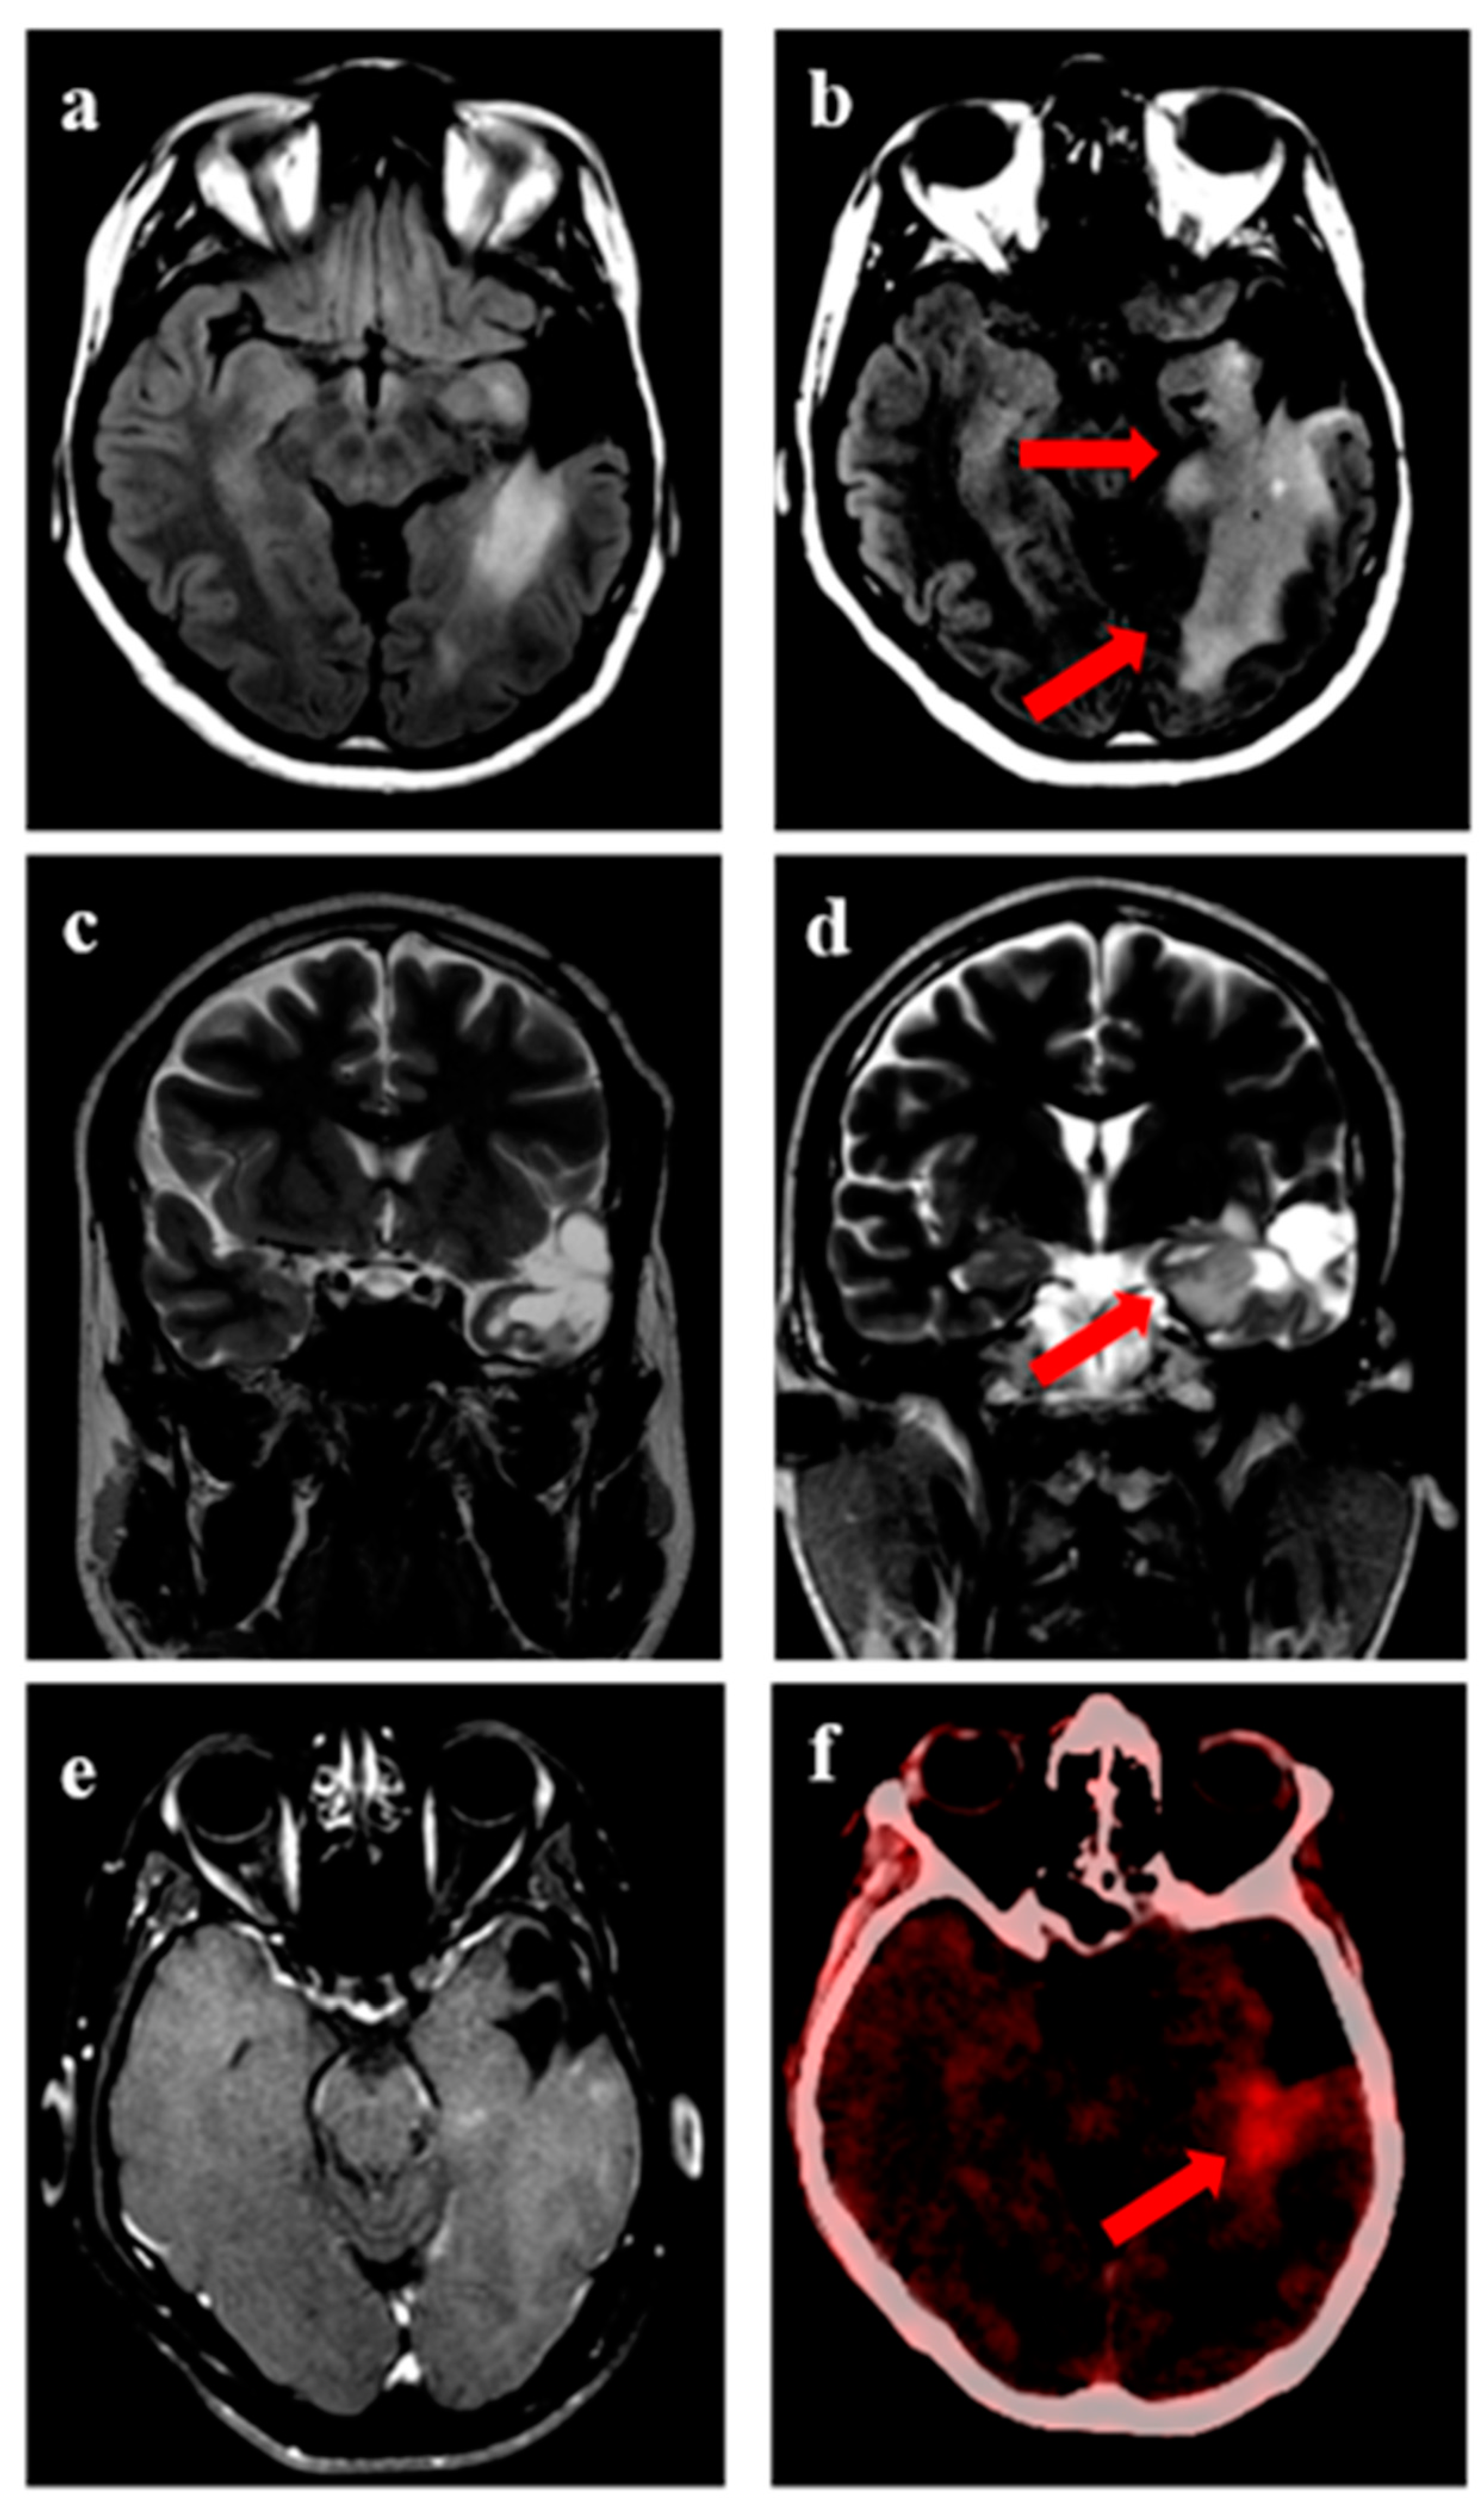

Figure 2.

Progression in a 32-year male with IDH-mutant astrocytoma. (a) shows residual disease following treatment completion, with (b) showing an increase in disease extent (arrow) after 7 years, as appreciated on axial T2-FLAIR sequences when reirradiation was considered. Representative images showing an increase in disease extent over medial extent of the cavity on coronal T2w sequence (c,d). (e) shows T1w-post gadolinium images showing no uptake of contrast in the area of new disease, suggesting absence of transformation to grade 4. (f) shows PET avidity over the area of active disease.